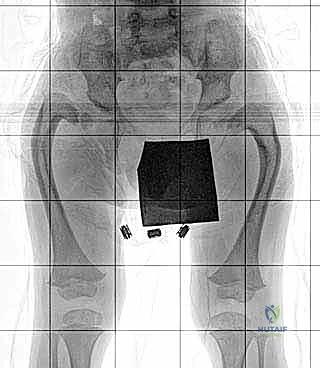

3. عمليات تطويل العظام المتقدمة (Bone Lengthening)

بعد التأكد من استقرار مفصل الورك والركبة، تبدأ مرحلة التطويل. يستخدم الدكتور هطيف أحدث التقنيات العالمية في صنعاء:

* المثبت الخارجي (Ilizarov / TSF): جهاز حلقي يثبت حول الساق، يتم من خلاله إجراء قطع عظمي دقيق (Corticotomy). يقوم الأهل بلف صواميل الجهاز يومياً بمقدار 1 ملم، مما يحفز الجسم على بناء عظم جديد في الفجوة (Distraction Osteogenesis).

| المرحلة الثالثة | 4 - 6 سنوات | الجلسة الأولى لتطويل عظمة الفخذ (عادة من 5 إلى 8 سم). | تقليل الفارق في الطول، تحسين المشية، البدء في العلاج الطبيعي المكثف. |

| المرحلة الرابعة | 8 - 12 سنة | الجلسة الثانية للتطويل (الفخذ و/أو القصبة)، تصحيح أي انحرافات محورية جديدة. | مواكبة نمو الطفل السريع، الحفاظ على استقرار المفاصل. |

| المرحلة الخامسة | 14 - 16 سنة | الجلسة النهائية للتطويل (غالباً باستخدام مسامير داخلية إن أمكن)، إيقاف نمو الطرف السليم جزئياً (Epiphysiodesis) إذا لزم الأمر. | الوصول إلى التساوي التام في طول الطرفين عند البلوغ واكتمال النمو. |